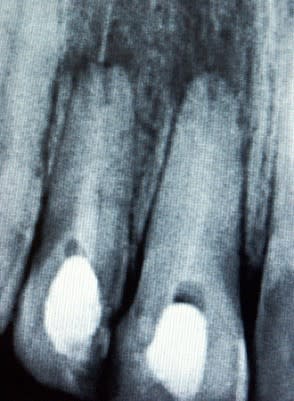

Puis j'ai fait des IC pour l'étancheité et des prov. Vous avez une radio à 1 mois post op pour controle. Les signes radios semblent montrer une régression des lésions.

Mais je ne sais pas s'il reste un peu de ciment infecté de l'ancienne endo au bout de la racine qui pourrait géner la cicatrisation totale.

Dois je envisager d'emblée une résection puis obtu MTA ou alors je laisse faire la nature.

Excuse mon audace Tonio mais, au vu des clichés, la racine de la 12 ne serait-elle pas fêlée?

je ne sais pas si la racine est fêlée, mais les endos sont belles.